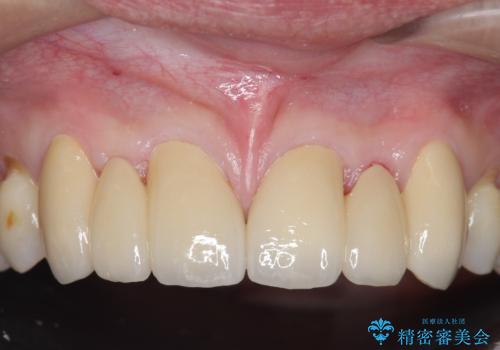

オールセラミッククラウン 部分矯正とセラミックによる前歯部の見た目の改善

- 前歯部のすきっぱと歯並びが気になるので診て欲しいといらっしゃった方の症例です。

全顎矯正は御希望されなかったため、上顎前歯部のみの部分矯正とオールセラミッククラウンによる補綴を行いました。

今回用いたオールセラミッククラウンはジルコニアフレームという白い素材の上にセラミックを盛っているため、審美性が非常に高いのが特徴です。